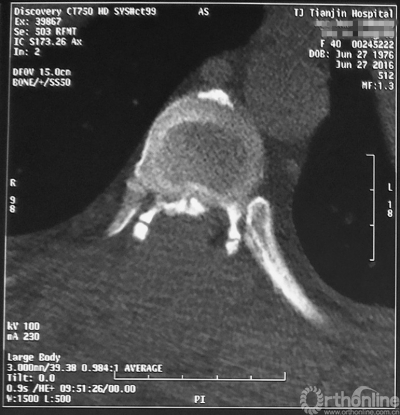

家人曾带她辗转当地治疗,因病情复杂没有得到有效的治疗,于是慕名找到天津医院脊柱外科二病区主任苗军博士诊治,当苗军主任看到躺在担架上的刘女士痛苦的表情和渴望健康的眼神,他决定收她入院为其进行手术治疗。入院检查发现,刘女士患有多节段胸椎管狭窄症,以胸8-9节段严重,椎管狭窄达80%,脊髓已严重变性。

术前MRI

术前CT